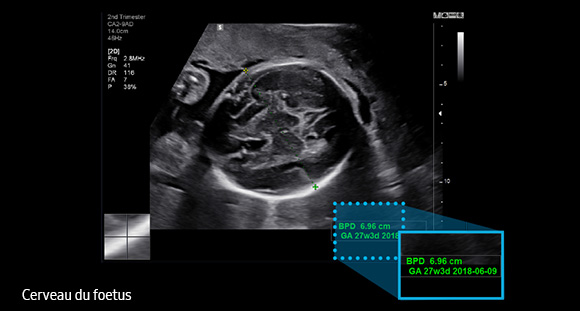

Le BiometryAssist™ est une technologie de biométries semi-automatisées qui permet à l'utilisateur de gagner en efficacité et en productivité.